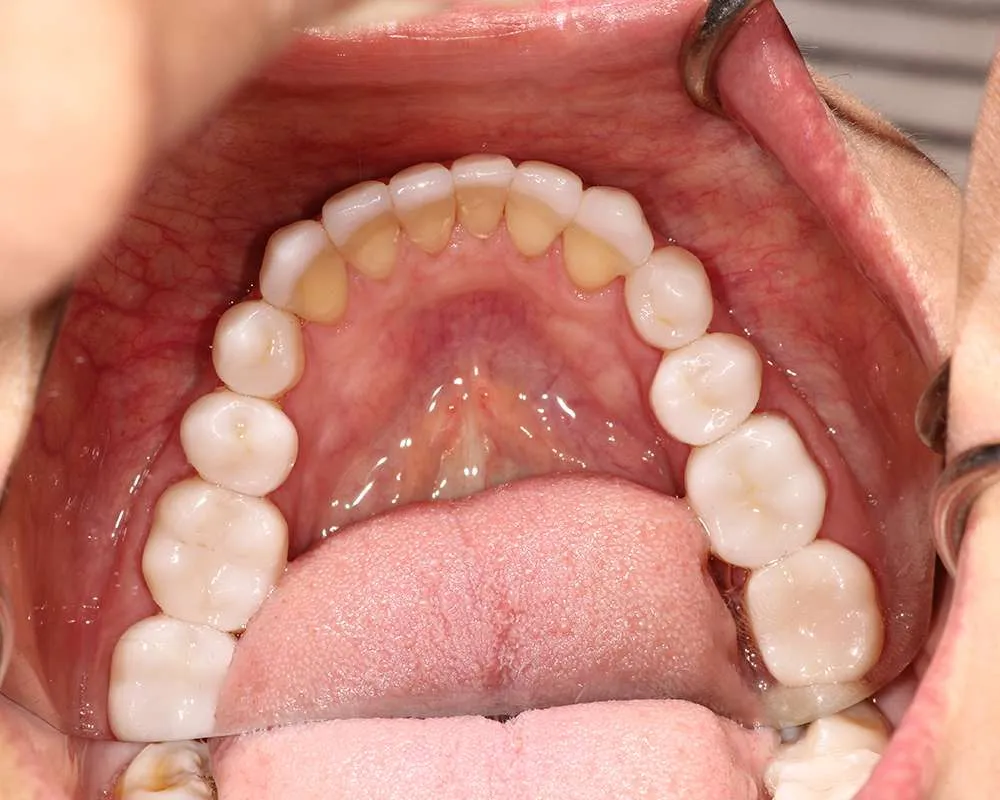

Real Stories, Real Results: Case Studies Showcasing How Our Personalized Approach Transforms Smiles and Lives

Complex Cases

Witness the Remarkable Changes We Can Achieve